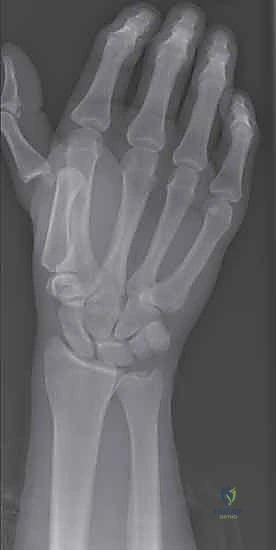

2. التصوير بالأشعة السينية (X-rays)

يُعد التصوير الشعاعي الخطوة الأولى لاستبعاد وجود كسور مصاحبة. في كثير من الأحيان، ينسلخ الرباط ويسحب معه قطعة صغيرة من العظم (Avulsion fracture). كما يتم أخذ صور أشعة تحت الإجهاد (Stress X-rays) لتوثيق عدم الاستقرار.